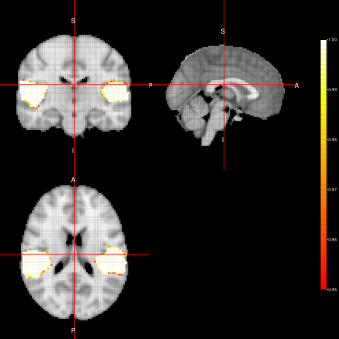

Marginal-FEST Joint-FEST

Refer to caption Refer to caption

ACE-FEST

Refer to caption

Figure 2: Activation Maps for the ”voice localizer” example obtained when using the FEST algorithm under three different distributions (Marginal, Joint and LTT) related to the state parameter.

From figures 2, 3 and 4, we can see the activation maps obtained for the ”voice localizer” experiment using the method proposed in this work. From those images, we can say that the three algorithms (FEST, FFBS and FSTS) under the three different distributions (Marginal, joint and LTT or average distribution) successfully identify the temporal activation due to voice and non-voice sounds stimulation, nevertheless there are some slight differences among those maps worth mentioning. For instance, the maps obtained when using the FFBS algortihm allows for the identification of a broader activated region from the temporal cortex, however, on the other hand, it allows activations to appear (false-positive activations) on brain regions that should not be involved with this ”voice localizer” experiment. On the other hand, more conservative results seem to be obtained when using FEST and FSTS algorithms, but with less false activations.